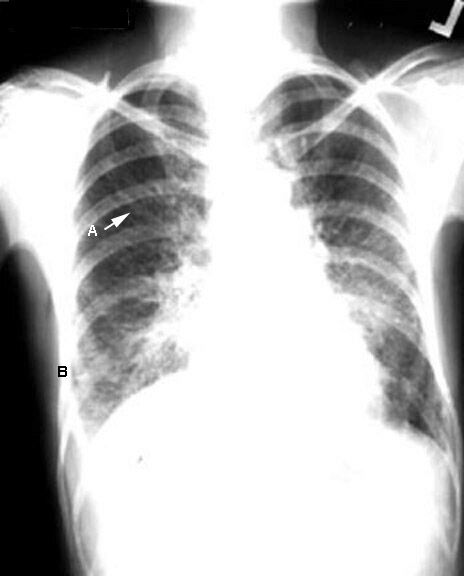

Kerley Lines

This is a case of cancer of the breast with

lymphangitic metastasis.

| A: |

Long wavy lines in upper and mid lung field |

| B: |

2-3 cm long pleural based in bases perpendicular to lateral

chest; reliable |

| C: |

Fine fibrillatory lines: You can imagine this on most cases |